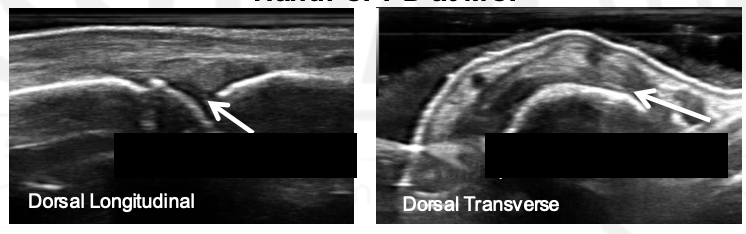

What view is this? What is the arrow?

DIP, tophus

MCP; Gout